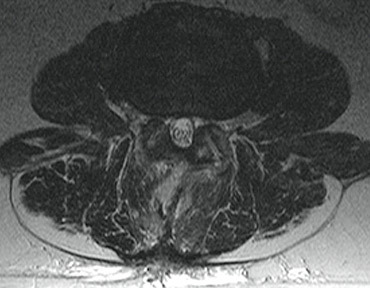

Εικόνα 3. Μετεγχειρητική μαγνητική τομογραφία όπου έχει γίνει άριστη αποσυμπίεση των νευρικών ριζών.

Εικόνα 2. Ελάχιστα επεμβατική μικροχειρουργική αποσυμπίεση.